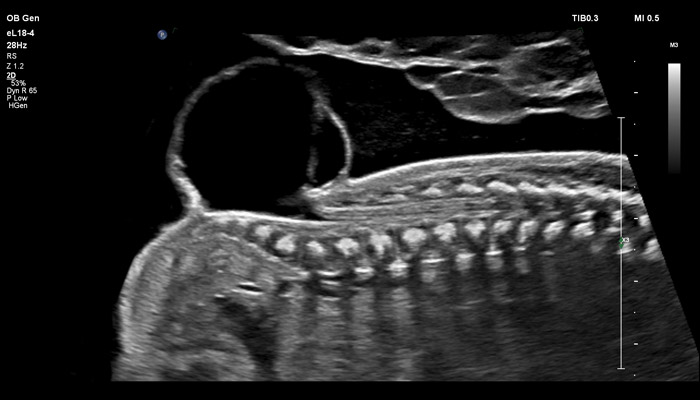

Начало новой жизни - это всегда особое время! Ультразвуковые решения Philips в области акушерства разработаны для того, чтобы позволить врачам сосредоточиться на здоровье каждой будущей мамы. Разработанные для обеспечения клиницистов дополнительной информацией ультразвуковые решения Philips позволяют получать не только детальную визуализацию анатомии плода уже в первом триместре, но и помогают оптимизировать рабочий процесс врача. Применение eL18-4 в I триместре беременности Сегодня ультразвуковая диагностика используется для выявления генетических аномалий, внутриутробных пороков, оценки жизнеспособности плода и определения срока беременности, как наиболее эффективный метод. Ультразвуковое исследование плода в первом триместре (до 13 недель 6 дней беременности включительно) является наиболее точным методом. В течение многих десятилетий трансвагинальный метод ультразвукового исследования был «золотым стандартом» диагностики в акушерстве. Сегодня линейный матричный датчик может стать альтернативой общепринятому трансвагинальному методу оценки состояния плода и репродуктивных органов женщины. Детальная анатомия плода и ранняя диагностика пороков в I триместре Ультразвуковое исследование является основным методом визуализации для оценки врожденных аномалий плода. Линейный матричный датчик eL18-4 позволяет получить детальную информацию об анатомии плода и выявить пороки на ранней стадии развития. Сверхширокополосная PureWave матрица датчика генерирует частоты в диапазоне 2-22 МГц, что формирует одинаково высокоинформативные, четкие изображения по всей глубине сканирования до 14 см.

До введения высокочастотных линейных датчиков точная ультразвуковая диагностика мочевой системы плода была доступна в основном после 16-17 недель беременности. Новая технология еL18-4 позволяет проводить раннюю морфологическую оценку плода уже в первом триместре. Клинический случай с применением eL18-4 демонстрирует, что кортико-медуллярная дифференцировка почек плода возможна на 14 неделе беременности”.

В случае аномалий позвоночника, оценка ануса важна, чтобы исключить аноректальные пороки развития, которые могут быть частью более широкой группы аномалий, известных как VACTERL (аномалии позвоночника, атрезия ануса, пороки сердца, трахеопищеводный свищ, аномалии почек, дефекты лучевой кости). Исследования в США показали, что очень высокое качество изображений еL18-4 повышают уверенность клиницистов в исключении аноректальной аномалии плода. Точная оценка состояния плаценты важна при определении сроков родоразрешения, а также при планировании хирургических вмешательств. Изображения показывают нормальный миометрий и четкую границу с плацентой. С визуализацией микрокровотока (MFI) хорошо представлены дугообразные артерии матери, спиральные артерии, а также ветвящиеся ворсинчатые артерии, что подтверждает нормально развитую сосудистую систему. Клинические исследования, проведенные экспертами детской больницы штата Аризона (США) во главе с Д-ром Льюсом Гонкалвсом с целью определения наличия нормальной сосудистой структуры плаценты при подозрении на ее патологию, показали, что инновационная технология сверхширокополосной PureWave матрицы датчика eL18-4 способна изменить привычный способ, которым врачи интерпретируют нормальный и аномальный сосудистый поток в плаценте.

Использование линейного матричного датчика eL18-4 при осмотре беременных в I триместре, особенно на ранних сроках, позволяет ограничиться трансабдоминальным сканированием вместо трансвагинального и при этом получить максимально полную диагностическую информацию. Отсутствие полостного исследования чрезвычайно важно для соблюдения принципа ALARA – использования минимальной необходимой мощности для безопасности пациента. Благодаря применению мультичастотного датчика с диапазоном от 2 до 22 МГц через переднюю брюшную стенку хорошо определяется эмбрион длиной 3 мм, что соответствует шестой неделе беременности. В конце I триместра с eL18-4 достаточно отчётливо визуализируется четырёхкамерный срез сердца, мочевой пузырь и сосуды пуповины, которые, как правило, определяются только при трансвагинальном сканировании.

Во II триместре беременности высокая разрешающая способность eL18-4 позволяет детально изучить структуру органов и тканей и увидеть многие нюансы, которые при работе другими датчиками не обнаруживались или становились очевидны в более поздние сроки. Например, у 19-недельного плода визуализируется перегородка носа, мышцы языка, диафрагма между грудной и брюшной полостью, на 20-й неделе чётко определяются оболочки спинного мозга и уретра, а на 24-й – хорошо дифференцируются корень лёгкого, борозды и извилины мозжечка и многие другие структуры.